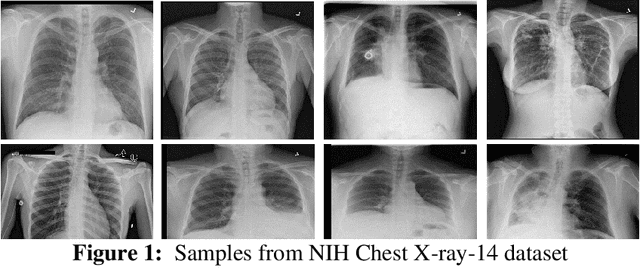

Abstract:Pneumothorax, a life threatening disease, needs to be diagnosed immediately and efficiently. The prognosis in this case is not only time consuming but also prone to human errors. So an automatic way of accurate diagnosis using chest X-rays is the utmost requirement. To-date, most of the available medical images datasets have class-imbalance issue. The main theme of this study is to solve this problem along with proposing an automated way of detecting pneumothorax. We first compare the existing approaches to tackle the class-imbalance issue and find that data-level-ensemble (i.e. ensemble of subsets of dataset) outperforms other approaches. Thus, we propose a novel framework named as VDV model, which is a complex model-level-ensemble of data-level-ensembles and uses three convolutional neural networks (CNN) including VGG16, VGG-19 and DenseNet-121 as fixed feature extractors. In each data-level-ensemble features extracted from one of the pre-defined CNN are fed to support vector machine (SVM) classifier, and output from each data-level-ensemble is calculated using voting method. Once outputs from the three data-level-ensembles with three different CNN architectures are obtained, then, again, voting method is used to calculate the final prediction. Our proposed framework is tested on SIIM ACR Pneumothorax dataset and Random Sample of NIH Chest X-ray dataset (RS-NIH). For the first dataset, 85.17% Recall with 86.0% Area under the Receiver Operating Characteristic curve (AUC) is attained. For the second dataset, 90.9% Recall with 95.0% AUC is achieved with random split of data while 85.45% recall with 77.06% AUC is obtained with patient-wise split of data. For RS-NIH, the obtained results are higher as compared to previous results from literature However, for first dataset, direct comparison cannot be made, since this dataset has not been used earlier for Pneumothorax classification.

Abstract:Among various medical imaging tools, chest radiographs are the most important and widely used diagnostic tool for detection of thoracic pathologies. Researches are being carried out in order to propose robust automatic diagnostic tool for detection of pathologies from chest radiographs. Artificial Intelligence techniques especially deep learning methodologies have been found to be giving promising results in automating the field of medicine. Lot of research has been done for automatic and fast detection of pneumothorax from chest radiographs while proposing several frameworks based on artificial intelligence and machine learning techniques. This study summarizes the existing literature for the automatic detection of pneumothorax from chest x-rays along with describing the available chest radiographs datasets. The comparative analysis of the literature is also provided in terms of goodness and limitations of the existing literature along with highlighting the research gaps which need to be further explored. The paper provides a brief overview of the present work for pneumothorax detection for helping the researchers in selection of optimal approach for future research.